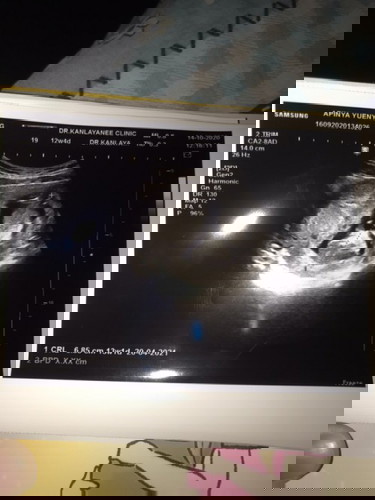

กำหนดคลอด25เมษายน2564